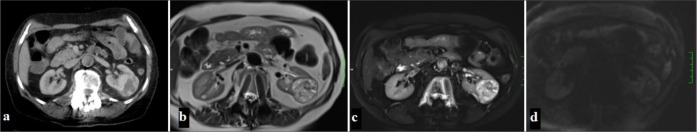

本文综述了计算机断层扫描(CT)和磁共振成像(MRI)对肾细胞癌(RCC)亚型的评价。肾细胞癌是一种具有不同组织病理学亚型的恶性肿瘤,约占成人肾肿瘤的90%。据报道,这些亚型在临床行为、治疗反应和预后方面存在显著差异。本研究比较了透明细胞RCC (ccRCC)、乳头状RCC (pRCC)、疏色RCC (chRCC)、髓质RCC (mRCC)、集管RCC (cdRCC)和多室囊性RCC (mcRCC)等亚型的CT和MRI表现。CT是RCC分期和手术计划的首选成像方法,可以提供肿瘤大小、血管分布和转移扩散的详细信息。另一方面,MRI由于其软组织分辨率和造影剂使用优势,可以更好地表征RCC亚型。该研究关注了每种亚型的不同影像学特征,并详细介绍了这些发现在临床决策过程中的作用。有研究表明,ccRCC在CT上表现为皮质髓质期强烈的对比增强和快速冲洗模式,在MRI上表现为T2A高信号和T1加权成像(T1A)低信号。据报道,pRCC具有低血管特征,对比度增强较低,边界均匀。据报道,chRCC的血管结构较少,在皮质-髓质期表现出适度的对比增强。据报道,mRCC具有侵袭性特征,通常在晚期诊断,而cdRCC具有非常侵袭性的临床病程。据报道,mcRCC在间隔之间含有明显的囊性区域,结构界限分明,通常具有低恶性潜能。因此,详细评估RCC亚型的CT和MRI表现对这些亚型的诊断、治疗和预后起着至关重要的作用。人们强调,本研究的发现将有助于开发更有针对性的肾细胞癌治疗方法。

This review discusses the evaluation of renal cell carcinoma (RCC) subtypes using computed tomography (CT) and magnetic resonance imaging (MRI). RCC is a malignancy with different histopathological subtypes, constituting approximately 90% of adult kidney tumors. It has been reported that these subtypes show significant differences in terms of clinical behavior, treatment response, and prognosis. In the study, CT and MRI findings of subtypes such as clear cell RCC (ccRCC), papillary RCC (pRCC), chromophobe RCC (chRCC), medullary RCC (mRCC), collecting duct RCC (cdRCC), and multiloculated cystic RCC (mcRCC) were compared. It was stated that CT is the first-choice imaging method in the staging and surgical planning of RCC and provides detailed information about the tumor size, vascularity, and metastatic spread. On the other hand, it has been emphasized that MRI allows better characterization of RCC subtypes with its soft-tissue resolution and contrast agent usage advantage. The study draws attention to the different imaging features of each subtype and details the role of these findings in the clinical decision-making process. It has been stated that ccRCC exhibits intense contrast enhancement and rapid washout pattern in the corticomedullary phase on CT and appears hyperintense on T2A and hypointense on T1 weighted imaging (T1A) on MRI. It has been stated that pRCC has hypovascular features, has lower contrast enhancement, and has homogeneous borders. It has been stated that chRCC has a less vascular structure and exhibits moderate contrast enhancement in the corticomedullary phase. It has been reported that mRCC has invasive features and is usually diagnosed at an advanced stage while cdRCC has a very aggressive clinical course. It has been stated that mcRCC contains distinct cystic areas between the septa, has a well-circumscribed structure, and generally has a low malignancy potential. As a result, it has been stated that detailed evaluation of CT and MRI findings of RCC subtypes plays a critical role in the diagnosis, treatment, and prognosis of these subtypes. It has been emphasized that the findings presented in this study will contribute to the development of more targeted treatment approaches in RCC management.